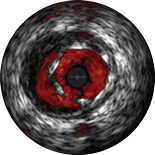

ChromaFlo provides easy assessment of stent apposition, lumen size and more by highlighting blood flow red at the touch of a button. ChromaFlo is available on Philips imaging systems.

Designed to make lumen size and stent apposition instantly recognizable and help identify branches, dissections, thrombus, and plaque distribution in bifurcations. ChromaFlo highlights blood flow red to identify:

No flushing and no special procedures are required during imaging. Simply activate ChromaFlo with a click.